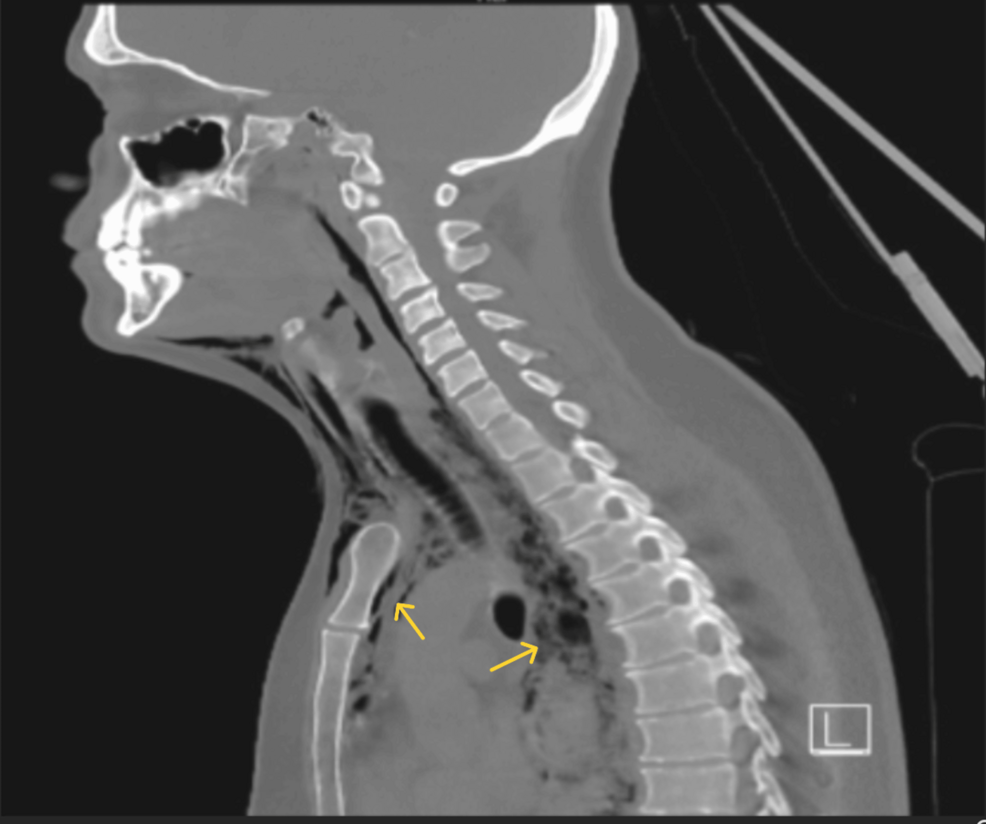

A Case of Esophageal Perforation Secondary to Undiagnosed Eosinophilic Esophagitis – Cureus